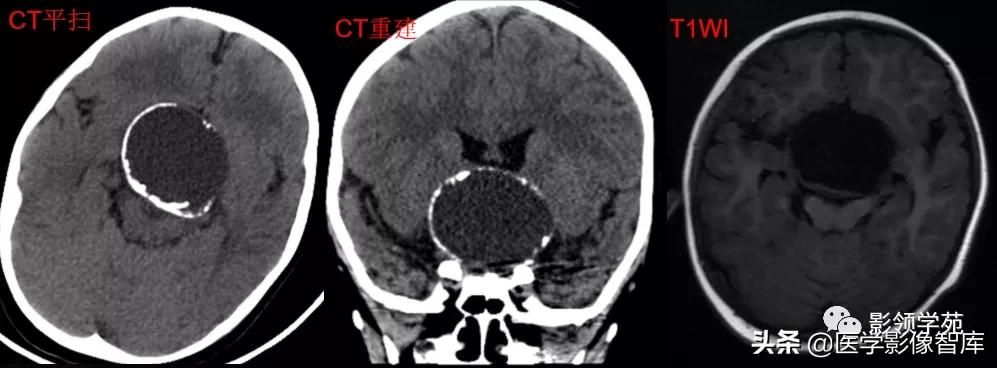

女 61岁 反复头晕3年余

鞍上可见一类圆形均匀稍高密度灶,CT值约47HU,

边界清楚,其内见一小点片状钙化灶;继发鞍上池受压伴变性。

鞍区占位肿块,呈等T1等T2信号,信号均匀,边界清楚。

病灶呈均匀、显著强化(馒头样),以宽基底与前颅窝底相连,

冠状位和矢状位见脑(硬)膜尾征;

肿块突入鞍上池,向上推压视交叉,后缘紧邻垂体柄,与双侧颈内动脉相邻。